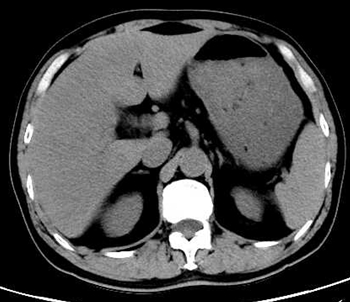

今晨零点左右上厕所后再发畏寒发热,家属发现其口唇发紫、呼吸急促,遂来本院急诊。腹部CT平扫提示肝内积气(图 2)。收住急诊抢救室,急查腹部增强CT,考虑肝脓肿致肝脏破裂(图 3)。

| 图 2 患者全腹部CT平扫示肝V段见团片状气体密度影(白色箭头所指处),腹腔可见大量游离气体(黄色箭头所指处) |

图 2患者全腹部CT平扫示肝V段见团片状气体密度影(白色箭头所指处),腹腔可见大量游离气体(黄色箭头所指处)。